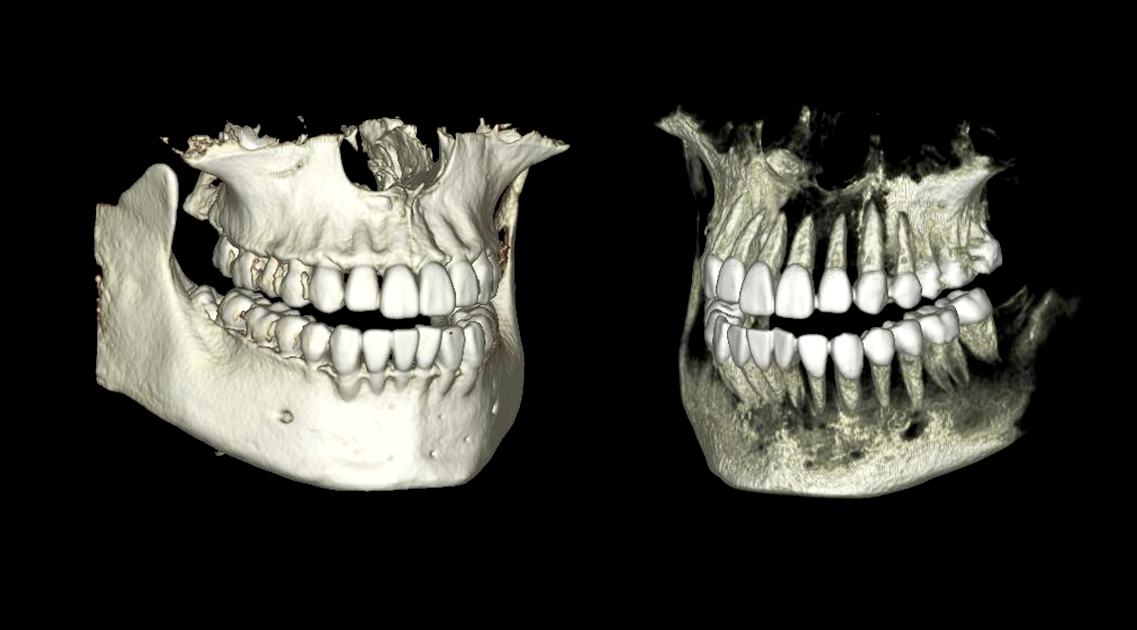

BioNaシミュレーション画像